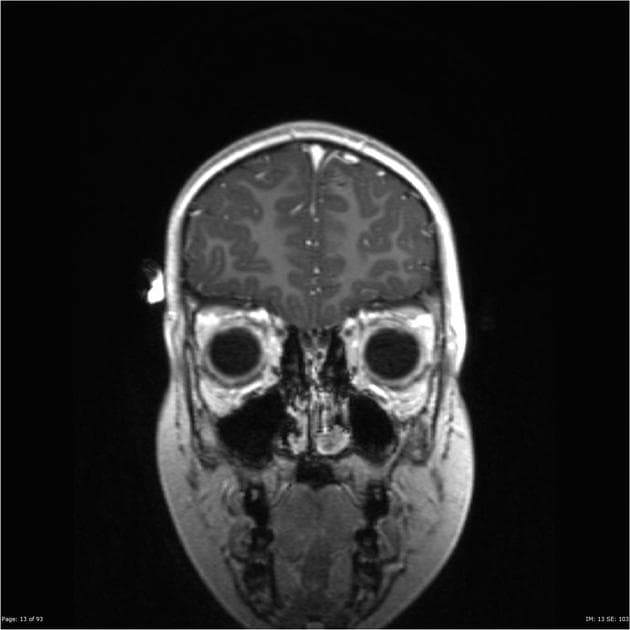

U xơ màng não vùng trên yên (Suprasellar meningioma)

Mù nửa đồng danh hai thái dương (bitemporal hemianopia). Tiền sử u xơ màng não vùng trên yên đã được cắt bỏ.

Tổn thương vùng trên yên kích thước 30 x 28 x 25 mm (TR x AP x CC), lan ra trước đến planum, làm mỏng và tách rộng giao thoa thị giác (optic chiasm), áp sát và đẩy hai động mạch cảnh trong (ICA) vào hai xoang hang về hai bên.

Đẩy tuyến yên (adenohypophysis) lệch xuống dưới.

Tổn thương hơi giảm tín hiệu trên T1, tăng tín hiệu trên T2, và cho thấy tăng quang (enhancement) mạnh.

Không thấy xâm lấn vào xoang hang (cavernous sinus).

- Khối tổn thương tăng quang mạnh ở vùng trên yên / planum sàng (suprasellar / planum sphenoidale), có hiệu ứng chiếm chỗ như mô tả, phù hợp với u xơ màng não vùng trên yên (suprasellar meningioma).

Bệnh nhân đã được cắt bỏ u xơ màng não vùng trên yên cách đây 5 năm, hiện nay có triệu chứng lâm sàng và hình ảnh học cho thấy gợi ý mạnh khả năng tái phát sau 5 năm.

U xơ màng não cần được đặt cao trong danh sách chẩn đoán phân biệt các tổn thương dạng đặc, tăng quang, ở vùng trên yên, với tín hiệu đồng nhất so với chất xám (isointense to grey matter) trên mọi chuỗi xung MRI.